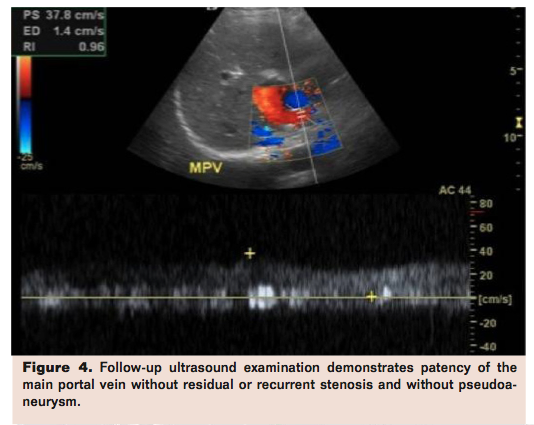

Patency of the portal vein may be evaluated with DUS and or cross-sectional imaging. Figures 1-4 show images from a case of a 34-year-old female with a history of liver transplant in 1994 due to autoimmune hepatitis and hepatitis, who presented with upper abdominal pain. Imaging evaluation with ultrasound followed by portal angiography was undertaken. Figures 1 and 2 show evaluation of patency.

Percutaneous transhepatic venoplasty is the first-line nonsurgical therapeutic approach for PVS as shown in Figure 3, but the portal vein can also be accessed via a transjugular approach. Multiple studies have examined the success of endovascular treatment in PVS. Shibata et al reported a success rate of 74% with a single session of balloon dilatation; the mean follow-up time was 24 months and 28% of patients suffered recurrent stenosis.8 In this study, the maximum number of dilation sessions needed to resolve the stenosis was three. Ko et al also reported a series of 9 patients who experienced early PVS following liver donor liver transplant.9 All patients were treated with transhepatic stent placement. At 66 months after placement, 6 of the 9 patients in the study demonstrated adequate stent patency. Notably, 2 post-procedural complications were reported, which included 1 case of intrahepatic pseuodaneurym and 2 cases of hemoperitoneum. Postprocedure patency may be assessed with DUS as shown in Figure 4.